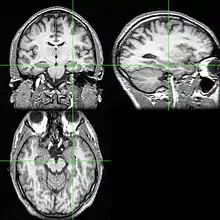

Neuroimaging tests may identify the cause for seizures and the seizure focus, the brain location where seizures begin.[4] In newly diagnosed epilepsy, magnetic resonance imaging (MRI) can detect brain lesion in up to 12 to 14% of persons with epilepsy.[30] However, for those with chronic epilepsy, MRI can detect brain lesion in 80% of the persons with epilepsy.[30] 3-Tesla MRI scan is advised for those with evidence of focal epilepsy such as temporal lobe epilepsy.[4] Abnormalities identified by MRI scan include hippocampal sclerosis, focal cortical dysplasia, other cortical developmental brain malformations, developmental and low-grade tumors, cavernous hemangioma, hypoxic-ischemic brain injury, traumatic brain injury and encephalitis.[4]